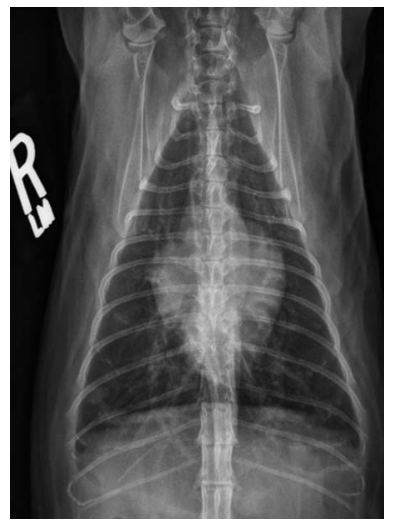

This appearance is most consistent with enlargement of which chamber(s)?

a) left atrium

b) left and right atrium

c) left ventricle

d) right ventricle

A

Valentine shaped heart can also occur with left and right atrium enlargement